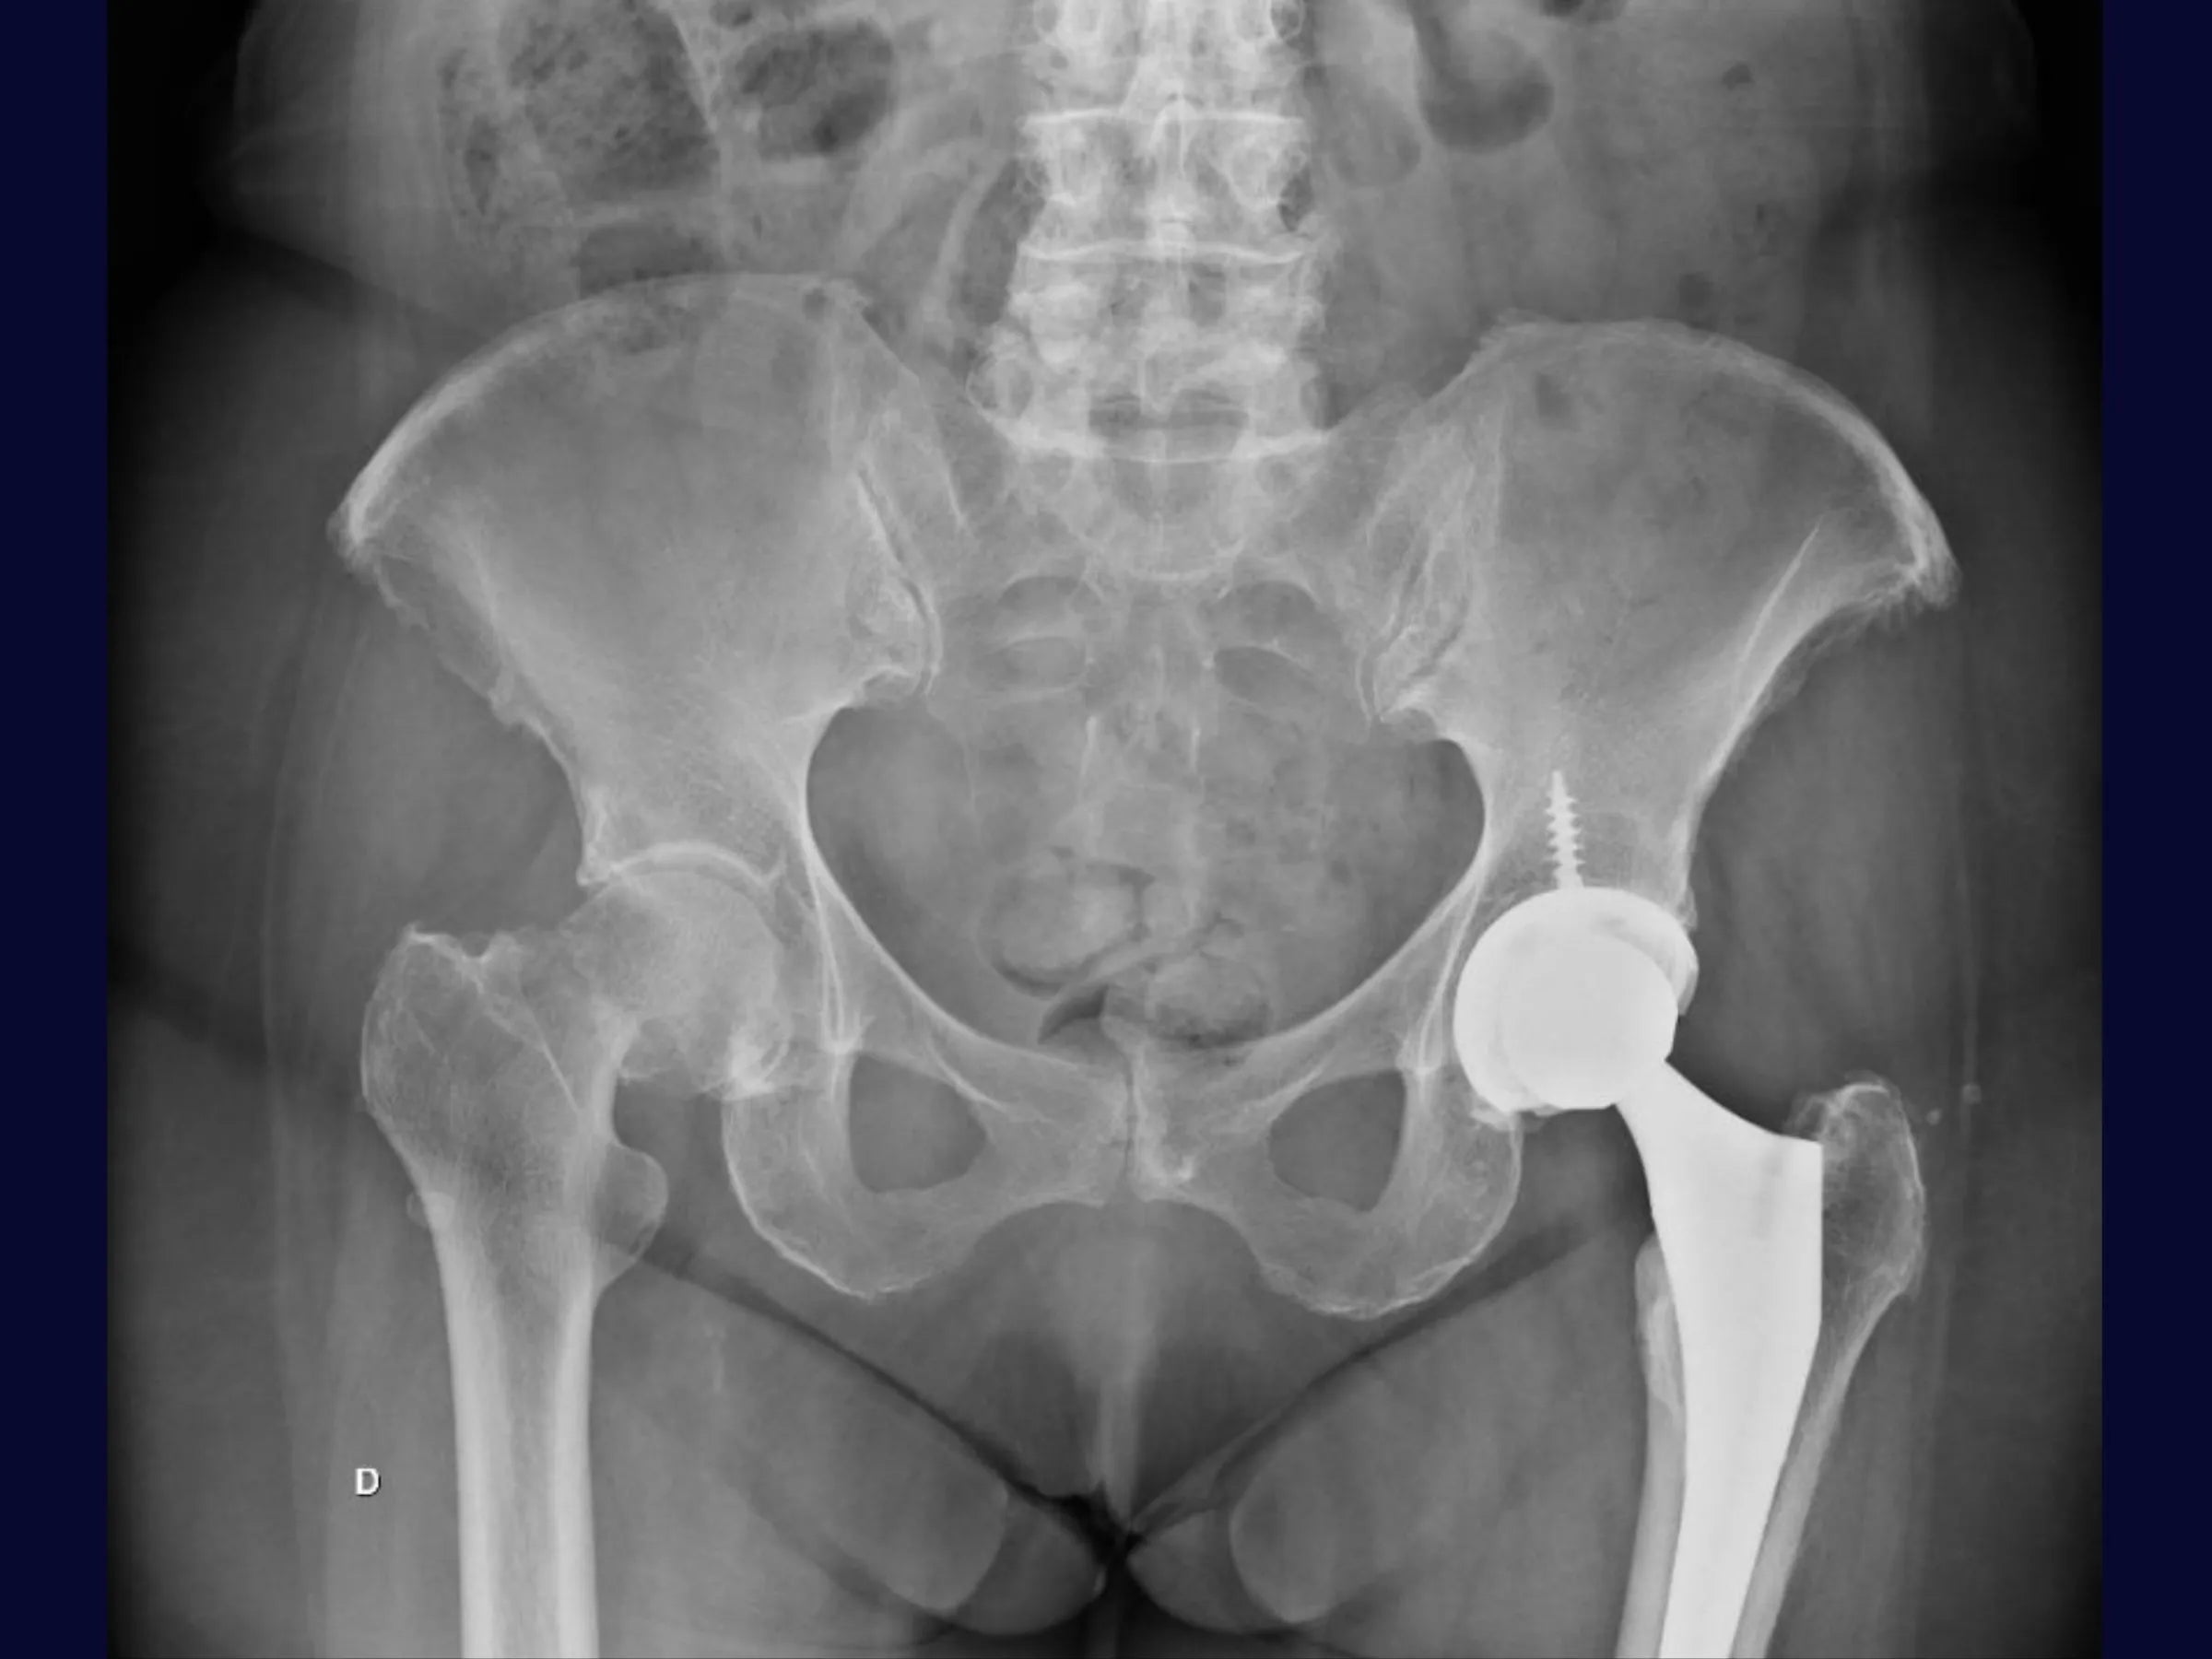

PDF Técnico Completo: inclui raio X, posicionamento do paciente, marcos anatômicos, instrumentais, critérios de estabilidade, algoritmos de decisão e cuidados pós-operatórios.